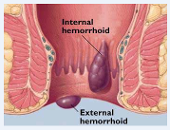

₦48,000.00Pile - Haemorrhoids,also known as piles, are swellings that contain enlarged blood vessel inside the rectum or anus